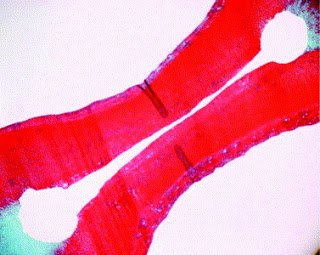

The middle and apical third are trickier to access. Often we are relying on our irrigation techniques to flush debris from the isthmus in the bottom third of the root. There are many supplemental disinfecting protocols on the market. Techniques range from the simplest plunging with a gutta percha cone (manual dynamic agitation) to using a complex vacuum system (apical negative pressure). I highly recommend readers familiarize themselves with Gu’s excellent review of irrigant agitation techniques found online here: http://www.endoexperience.com/userfiles/file/review_of_irrigation_agitation.PDF. In a research project at MCG, we found apical negative pressure (using the Endovac) to be slightly more effective than manual dynamic agitation at removing isthmus debris (Susin 2010). More importantly, we found neither technique could consistently produce clean isthmus histology slides like this one reproduced from this article by Gutarts, Nusstein, Reader, and Beck (reprinted